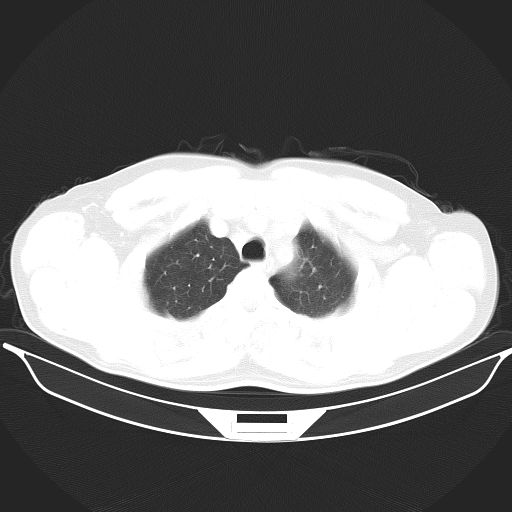

标题: CT25490:男,40岁,体检发现;无其它不适。 [打印本页]

标题: CT25490:男,40岁,体检发现;无其它不适。

考虑右下肺周围性肺癌并肺内多发转移,纵隔淋巴结转移!

支持 !考虑右下肺周围性肺癌并肺内多发转移,纵隔淋巴结转移,(气管前腔静脉后,隆突下,主动脉弓下都有了)